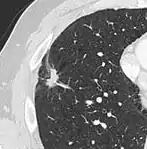

Thin slice and maximal intensity projection of a lung nodule, the latter better visualizing vascular convergence.[9]